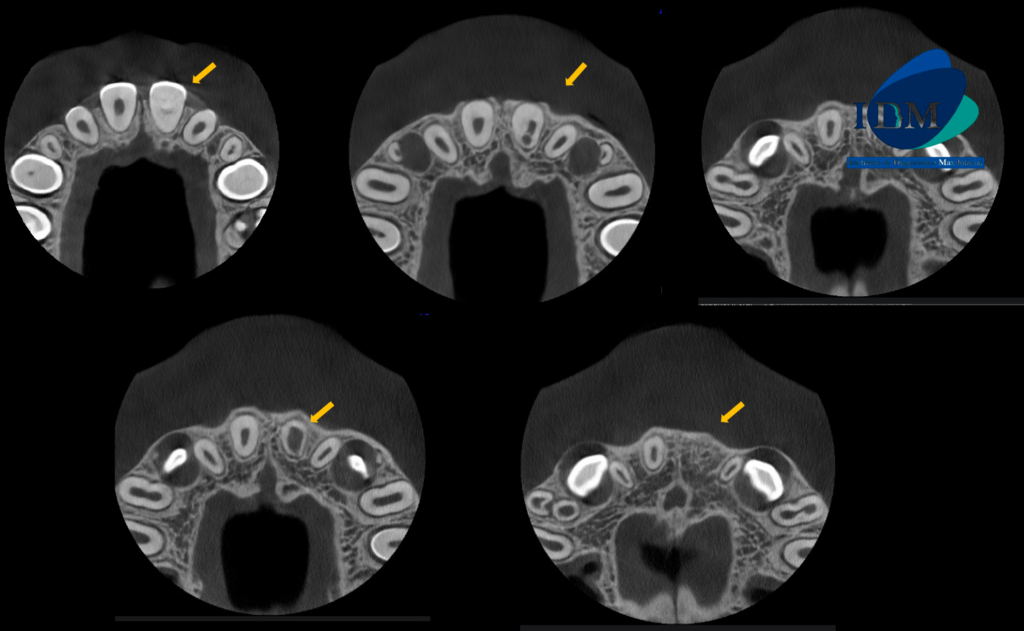

A la evaluación de la tomografía volumétrica (cone beam) de campo reducido en los cortes axiales (Figura 2) y transaxiales (Figura 3) se observa la pieza 21 con material restaurador coronal, obliteración de cámara y conducto radicular en tercio cervical y medio; además de observar la formación radicular incompleta caracterizado por tercio apical de conducto y foramen apical amplio; signos compatibles con secuela de trauma dental.

CORTES AXIALES

CORTES TRANSAXIALES